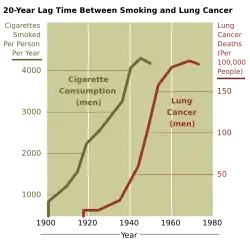

Produtos químicos

A exposição a determinadas substâncias tem sido associada a tipos específicos de câncer. Estas substâncias são denominadas cancerígenas. O tabagismo, por exemplo, é a causa de 90% dos casos de câncer de pulmão,[47] podendo ser também a causa de câncer de laringe, cabeça e pescoço, estômago, bexiga, rins, esôfago e pâncreas.[48] O fumo do tabaco contém mais de 50 agentes cancerígenos conhecidos, incluindo nitrosaminas e hidrocarbonetos aromáticos policíclicos.[49] O tabaco é responsável por cerca de uma em cada três mortes por câncer no mundo desenvolvido[50] e cerca de uma em cada cinco mortes em todo o mundo.[49] As taxas de mortalidade por câncer de pulmão nos Estados Unidos têm espelhado padrões, com o aumento de fumantes seguido por aumentos dramáticos nas taxas de mortalidade por câncer de pulmão. No entanto, a diminuição nas taxas de tabagismo desde a década de 1950 levou a decréscimos nas taxas de mortalidade por câncer de pulmão em homens desde os anos 1990.[51][52]